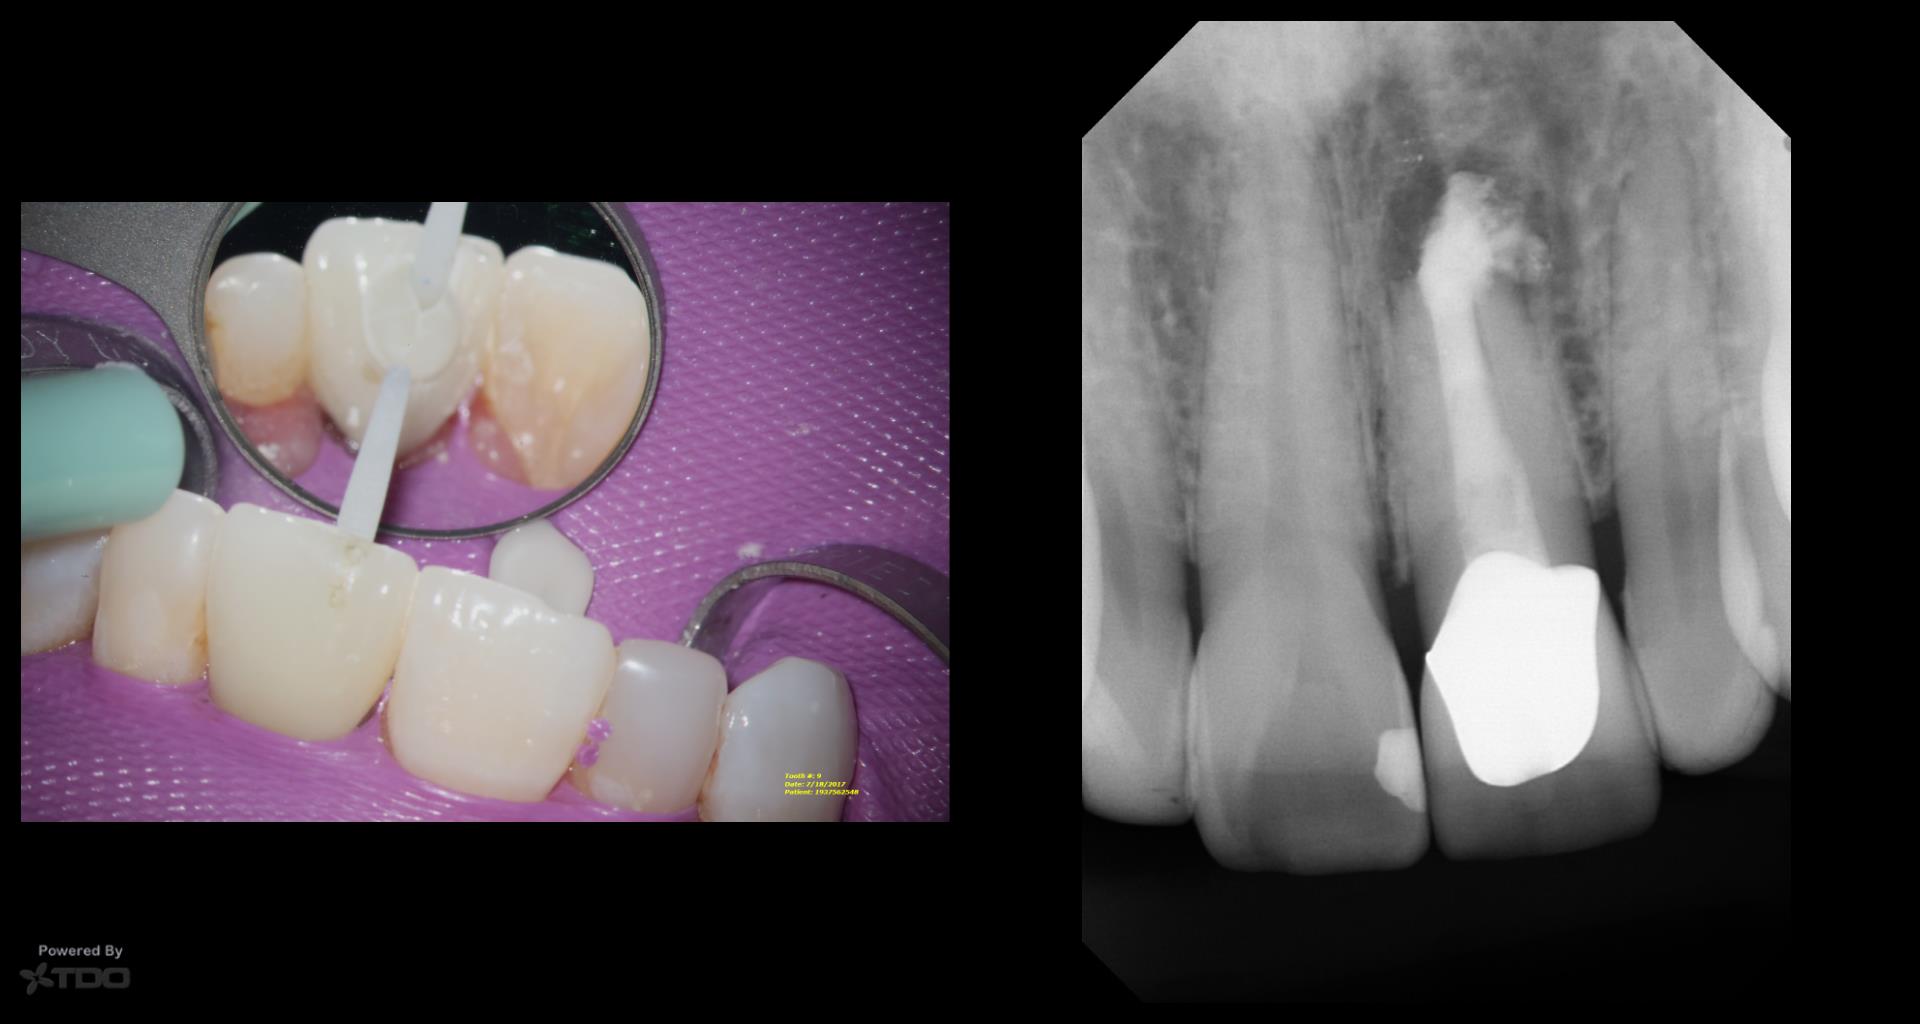

This was interesting because a root frac ture was seen where the prior apico was done. The MTAS was removed and Brassler putty used in this case. Will take a 1 yr CBCT and we will know more. Don’t usually get so much scar formation–so this was surprising…..